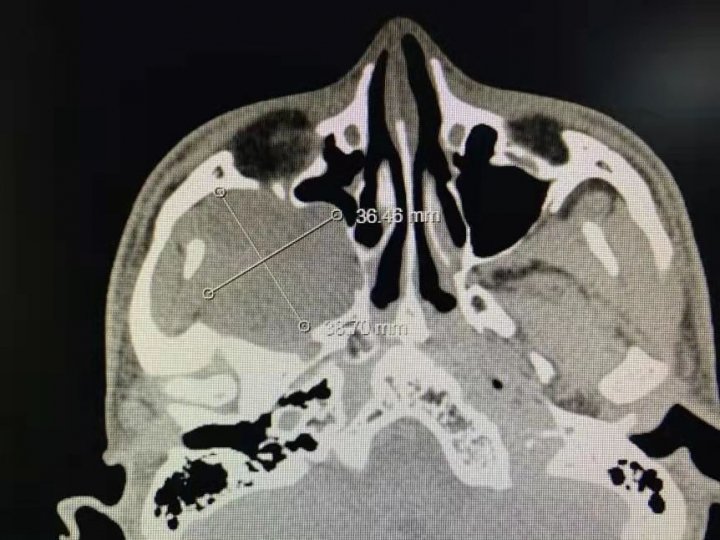

近日,延大附院口腔颌面外科高志彪副主任接诊了一名来自宁夏的25岁男性患者,该患者以右侧颊部肿胀伴张口受限9个月主诉入院。入院后行增强CT检查显示,右侧翼腭窝-咀嚼肌间隙-颌面部软组织肿瘤,大小约为5.0cm X3.0cm X3.0cm,肿瘤巨大,突向颊部并压迫下颌骨喙突,致患者张口受限,影响患者面容、吞咽及进食。

术前增强CT